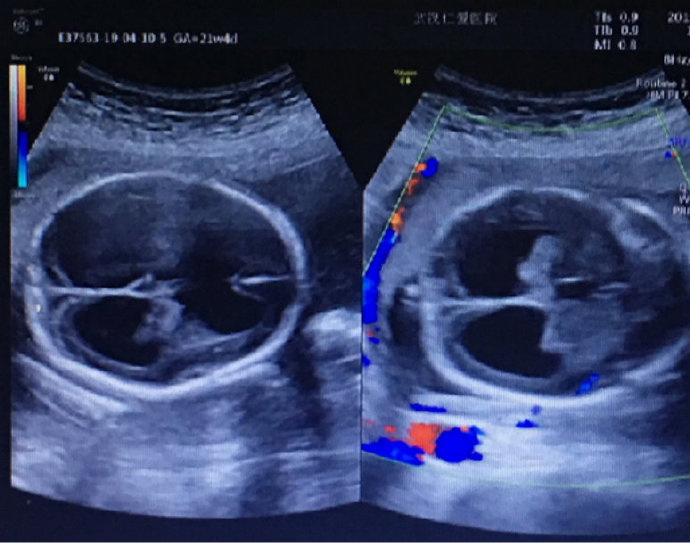

懷孕期間是每個女人一生中最重要的時期,可是有些孕婦懷孕期間亂用藥卻導(dǎo)致終生遺憾。最近武漢就有一名孕婦,在孕早期因感冒、胃疼亂吃了很多消炎和止痛藥,結(jié)果在孕22周···